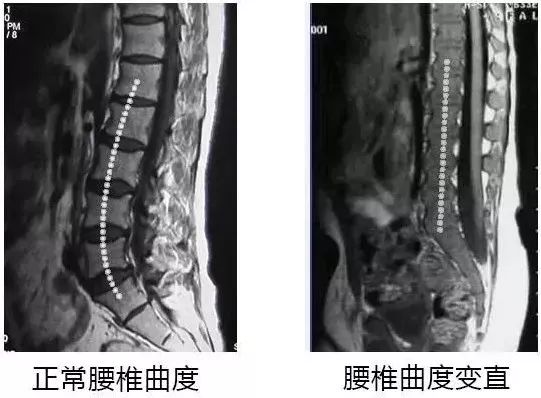

腰椎间盘变直,反弓

腰肌乏力疼痛等

背部僵硬,肢体麻木,跛行,甚至下肢瘫痪

德国世琉家研究团队

根据人体工学结构设计

按照腰椎科学角度生理弯曲值

打造了一款贴合腰背脊椎曲线,舒适减压的腰靠